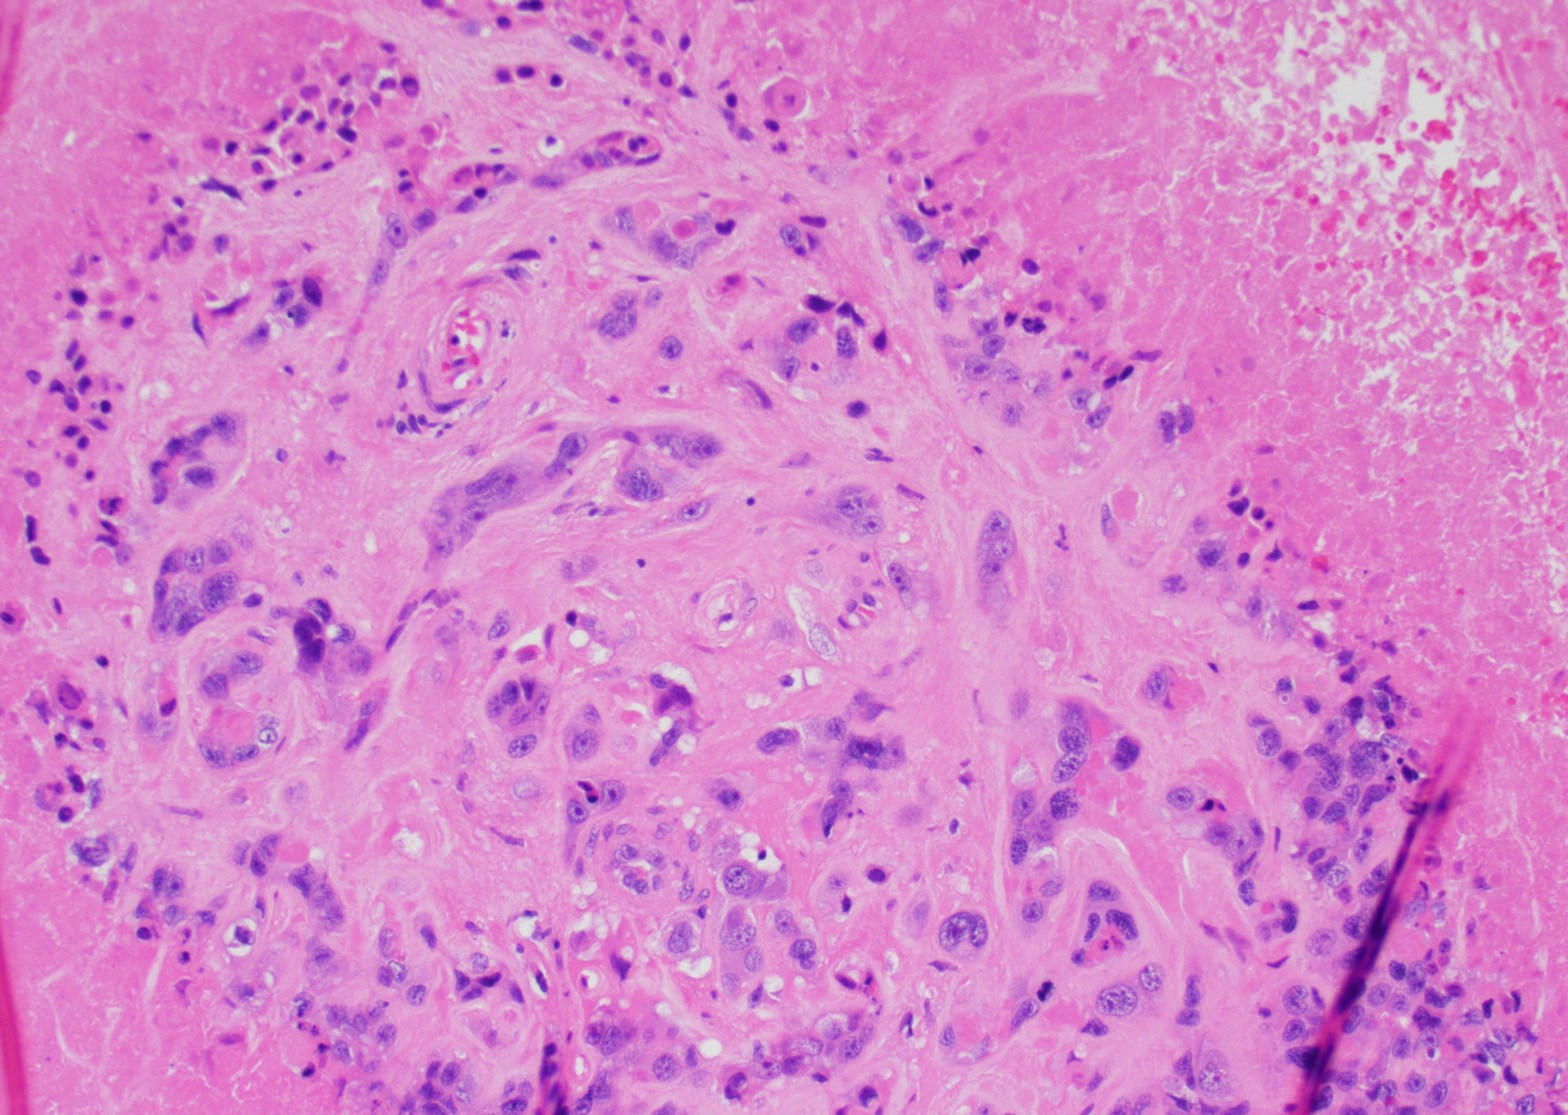

A 47-year-old woman with prolonged uterine bleeding and initial endometrial sampling with proliferative endometrium. Because of her prolonged uterine bleeding and leiomyomatous uterus she was taken to the operating room and hysterectomy was performed. Grossly, the uterus revealed multiple leiomyomas, but also a white-tan lesion in the lower uterine segment. Microscopic examination: the lesion revealed nodular, expansile growth. The nodules were composed of epithelioid cells with abundant eosinophilic cytoplasm, frequent mitotic figures, and the backgroundContinue reading “Epithelioid Trophoblastic Tumor and Differential Diagnoses”